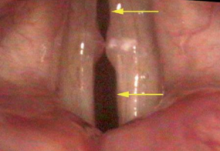

During an examination, people hate to be embarrassed--they naturally and fairly immediately try to compensate for any hoarseness. It is fortunate that there is redundancy in the vocal system so compensation is usually available to maintain sound production even when there is a problem. However, for the examiner, compensation tends to hide a voice disorder, both audibly as well as visually. Some common instances hidden by compensation include mucosal disorders on the edge of the vocal cord or weakness from neurologic and muscular disorders.

If you are hoarse, almost certainly you will benefit from a video recording of your vocal cords. Most vocal events happen too fast for you to perceive, without some capability to slow and review the images of a video recording. Even video needs some help from a stroboscope or high-speed recording to catch events well.